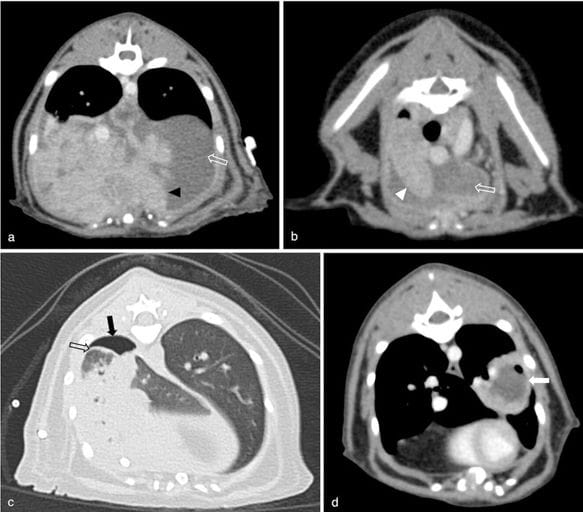

Examples of CT findings in our population: (a) irregular soft tissue-attenuating, contrast-enhancing bands within the pleural space consistent with marked pannus formation (black arrowhead); (b) pneumonia characterised by increased pulmonary parenchymal attenuation and maintained lung volume (white arrowhead); (c) thickening of the visceral pleura (black hollow arrow), best visualised in the lung window and in this instance highlighted by adjacent pneumothorax; (d) abscess formation with intralesional gas (white arrow) in the left caudal lung lobe. Pneumothorax (black arrow) and pleural effusion (white hollow arrow) can be seen in multiple images